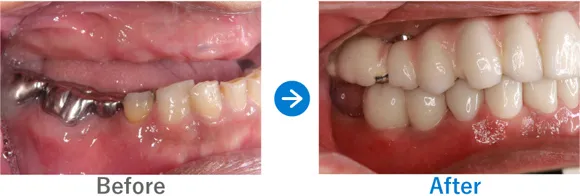

Case8

重度の歯周病で歯並びにも影響が。オールオン4で噛み合わせも改善

残存歯の動揺、義歯の不適合、重度の歯周病

上顎 オールオン4、下顎 オールオン4

7,150,000円(上顎3,575,000円、下顎3,575,000円/内訳:オールオン4(ストローマン)、3Dモデルガイド*、仮歯、セデーション、ボツリヌストキシン注射、3D模型、保証10年)

来院の背景

残っている歯がぐらぐらする感覚があり、使用中の義歯が合わなくなってきているため、インプラントを検討し来院されました。

治療結果

もともと重度の歯周病があり、残っている歯が動いてしまい歯が前に出ているような並びになっていました。そのため、正常な位置で嚙み合わせるように設計し、オールオン4治療を行いました。歯周病に加え喫煙も続けているため、インプラント周囲炎にはとくに注意が必要です。